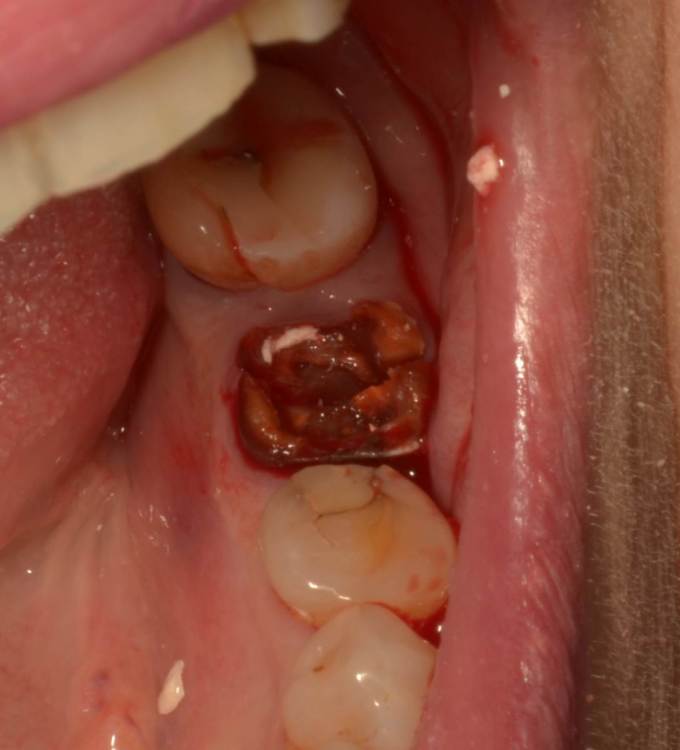

Большой Зеленый Опубликовано 20 мая, 2022 Поделиться Опубликовано 20 мая, 2022 Примерно 80 процентов . Просто не всегда удается сохранить перегородку . Она вроде бы есть ,а на деле все выгнило. Очень часто это не просто трещины корня, это огромные дефекты . Смысла нет толкать имплант в гной.. Ссылка на комментарий

pit Опубликовано 26 мая, 2022 Поделиться Опубликовано 26 мая, 2022 16.05.2022 в 08:01, chervoncevdaniil сказал: коллеги,можете пояснить,пожалуйста,как вы принимаете решение когда в боковом отделе можно удалить и сразу поставить имплант,удалить+костная пластика и сраазу имплантация,а когда идете отсрочено после удаления?какие основные критерии? 1. Отсутствие острого процесса 2. Достаточное количество мягких тканей 3. Возможность стабилизации импланта с расстоянием до вестибулярной стенки не менее 2 мм. Костная пластика (IDR), чаще НКР при утрате или повреждении вестибулярной стенки, но с сохранением мягких тканей. Ссылка на комментарий

pit Опубликовано 26 мая, 2022 Поделиться Опубликовано 26 мая, 2022 8 часов назад, Большой Зеленый сказал: А если стенки вестибулярной нет не будешь ставить? Буду и создам ее с помощью НКР или ИДР) Ссылка на комментарий

Большой Зеленый Опубликовано 27 мая, 2022 Поделиться Опубликовано 27 мая, 2022 Аналогично..) 4 1 Ссылка на комментарий